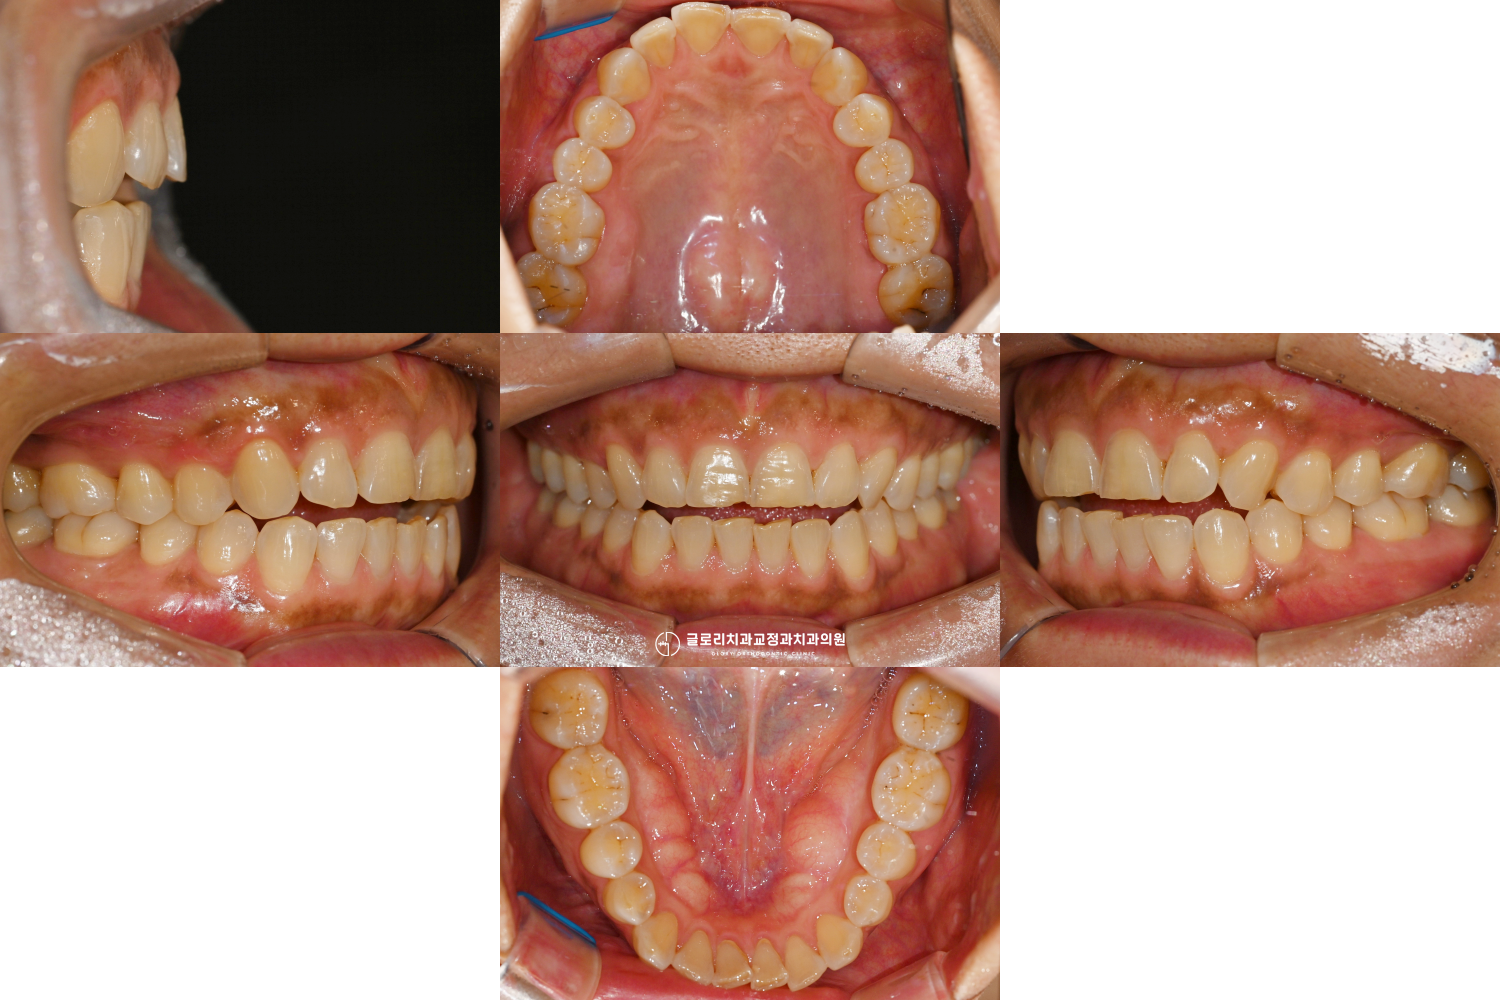

초진 단계 – 개방교합과 상,하악 총생

망우동 교정치과 에서 앞서 확인한 구강 모습과 골격적인 모습을 관찰해 보면,

Normodivergent pattern으로 정상적인 수직 골격 패턴을 보여줍니다.

즉, 세로로 과도하게 긴 유형(High angle)이 아니므로,

어금니 과맹출로 인한 전형적인 골격성 개방교합의 가능성은 아닌 것으로 판단됩니다.

다만, Skeletal Class II 관계를 보이고 있으며,

이는 상악의 전방 위치와 하악의 후퇴가 동반된 전후방 부조화를 의미합니다.

치아 각도를 살펴보면 상악 전치는 후방 경사를 보이는 반면,

하악 전치는 과도한 전방 경사를 보이고 있습니다.

이러한 전치부의 불균형은 절단면 간의 정상적인 수직적 접촉을 방해하게 되며,

그 결과 수직 피개(overbite)가 감소하고 전치부 개방교합이 형성된 것으로 판단됩니다.

또한 상·하순이 E-line 대비 전방에 위치해 있어,

전치의 전방 위치와 연조직 돌출이 함께 나타난 상태로 해석할 수 있습니다.

망우동 교정치과 사진을 보면 구강 내 공간이 비교적 충분하며,

특히 상악은 필요시 사랑니 발치를 통해

추가적인 후방 여유 공간 확보도 가능한 상황입니다.